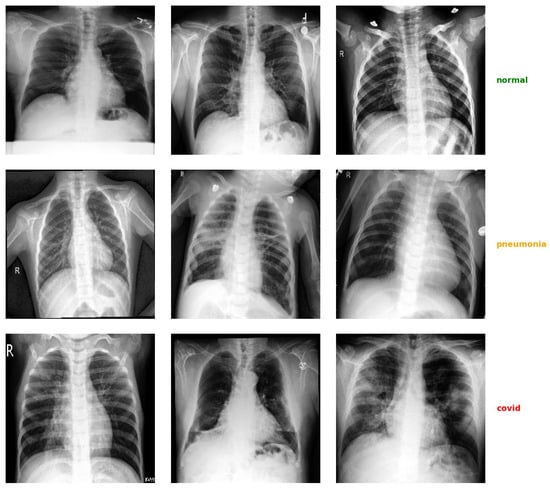

3.1. Dataset